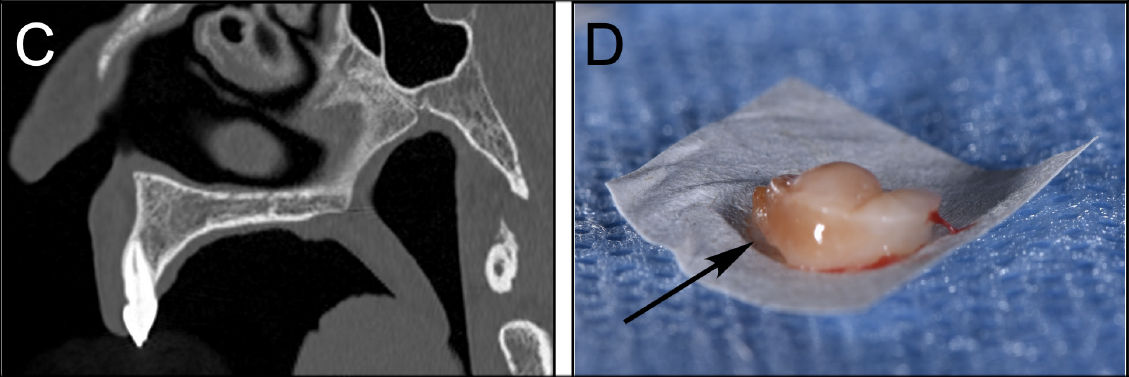

Фото 1. (C) — КТ верхней челюсти не выявила вовлечения костной ткани неба; (D) — В биоптате отмечается бурое окрашивание из-за отложения гемосидерина в соединительной ткани (стрелка)

При осмотре выявлен одиночный красноватый, безболезненный, подслизистый узелок с дольчатой поверхностью в средней части заднего отдела твёрдого неба. Пациентка пользовалась частичным съёмным протезом, не контактировавшим с очагом. При пальпации образование было мягким, покрывающий эпителий не изъязвлён, поражение прочно фиксировано к подлежащим тканям. КТ верхней челюсти не выявила вовлечения костной ткани неба.

Была выполнена инцизионная биопсия. Образец показал выраженное отложение гемосидерина в соединительной ткани. Микроскопически отмечен плотный, смешанный воспалительный инфильтрат в собственной пластинке слизистой, состоящий из лимфоцитов, макрофагов, плазматических клеток, нейтрофилов и эозинофилов. Инфильтрат был диффузным, с акцентом вокруг мелких сосудов, проникал в сосудистые стенки, вызывая лейкоцитоклазию и очаговый фибриноидный некроз.